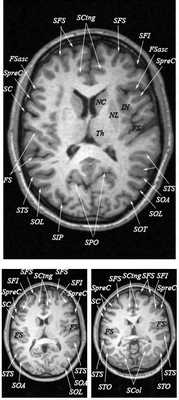

Анатомия головного мозга в МРТ изображении

МРТ головного мозга. Т2-взвешенная аксиальная МРТ. Цветовая обработка изображения.

Знание анатомии мозга очень важно для правильной локализации патологических процессов. Ещё более важно оно для изучения самого мозга с помощью современных «функциональных» методов, таких как функциональная магнитно-резонансная томография (fMRI), и позитронно-эмиссионная томография. С анатомией мозга мы знакомимся ещё со студенческой скамьи и существует множество анатомических атласов, в том числе и поперечных сечений. Казалось бы, зачем ещё один? На самом деле, сравнение МРТ срезов с анатомическими приводит к множеству ошибок. Это связано как со специфическими особенностями получения МРТ изображений, так и с тем, что строение мозга очень индивидуально.

Представленная страница сайта основана на специальном изучении МРТ головного мозга здоровых лиц. Для этого изображения получали с минимальной величиной воксела (1 мм в каждом измерении), что исключало наслоения борозд. Каждая из структур прослеживалась в трёх реконструированных плоскостях путём её выделения с помощью компьютерной программы. Мы рассматривали различные анатомические варианты, что обсуждается в работе. В результате, учитывая вариабельность строения мозга, подобран условно «стандартный» мозг. Поскольку на сайте нереально представить 128 срезов в каждой из основных плоскостей, мы ограничились только каждым пятым срезом. Основные срезы в поперечной плоскости даны без наклона назад (угол 0º). Под ними для представления о изменении соотношения анатомических структур демонстрируются срезы, выполненные на тех же уровнях, но с наклонами назад -15º и -30º.

Список сокращений

Борозды

Междолевые и срединные

SC - центральная борозда

FS - Сильвиева щель (латеральная борозда)

FSasc - восходящая ветвь Сильвиевой щели

FShor - поперечная борозда Сильвиевой щели

SPO - теменно-затылочная борозда

STO - височно-затылочная борозда

SCasc - восходящая ветвь поясной борозды

SsubP - подтеменная борозда

SCing - поясная борозда

SCirc - круговая борозда (островка)

SpreC - предцентральная борозда

SparaC - околоцентральная борозда

SFS - верхняя лобная борозда

FFM - лобно-краевая щель

SOrbL - латеральная глазничная борозда

SOrbT - поперечная глазничная борозда

SOrbM - медиальная глазничная борозда

SsOrb - подглазничная борозда

SCM - мозолисто-краевая борозда

SpostC - постцентральная борозда

SIP - внутритеменная борозда

STS - верхняя височная борозда

STT - поперечная височная борозда

SCirc - круговая борозда

SCalc - шпорная борозда

SOL - латеральная затылочная борозда

SOT - поперечная затылочная борозда

SOA - передняя затылочная борозда

Поперечные (аксиальные) МРТ срезы головного мозга